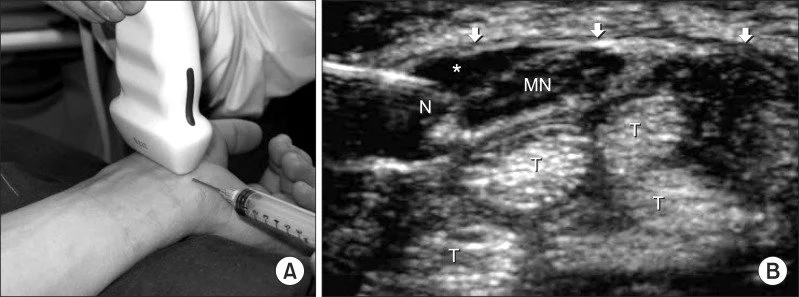

A guided corticosteroid injection into the carpal tunnel can reduce swelling around the nerve. At our clinic, this is performed with ultrasound guidance to enhance precision and effectiveness.

Ultrasound-guided carpal tunnel injection Phoenix

Ultrasound-guided corticosteroid injection for carpal tunnel syndrome.